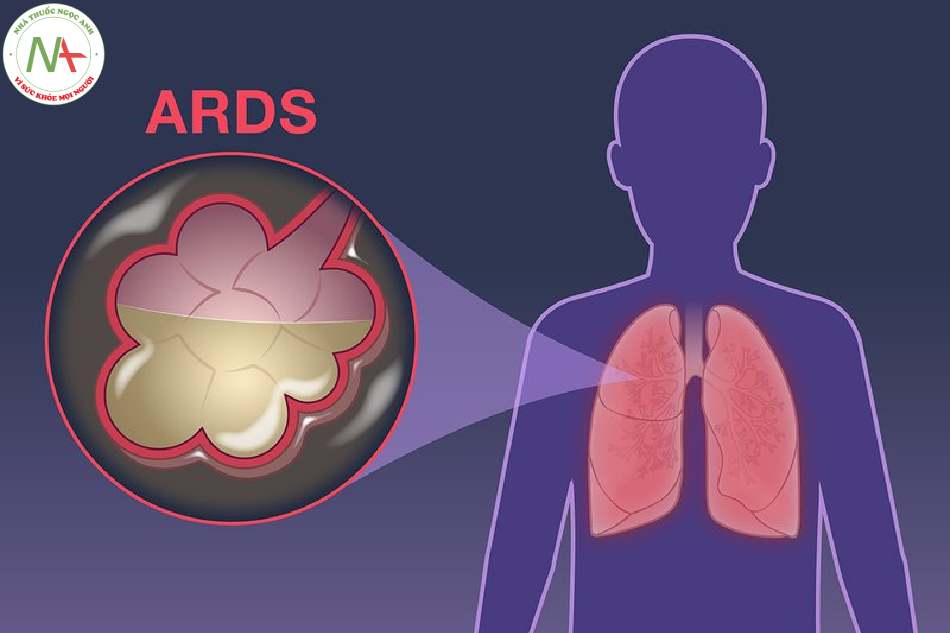

Hội chứng suy hô hấp cấp tiến triển (ARDS) được Ashbaugh và cộng sự mô tả lần đầu tiên năm 1967. Là một hội chứng bệnh lý trong đó màng phế nang mao mạch của phổi bị tổn thương cấp tính do nhiều nguyên nhân khác nhau dẫn đến tình trạng suy hô hấp nặng không đáp ứng với thở oxy liều cao.

Năm 1994, hội nghị đồng thuận Âu- Mỹ (AECC) đã đưa ra định nghĩa về hội chứng suy hô hấp cấp tiến triển ARDS. Từ đó, đã có nhiều công trình nghiên cứu về giá trị và tính ứng dụng của định nghĩa này trên lâm sàng. Năm 2011, hội nghị gồm các chuyên gia hàng đầu đã đưa ra định nghĩa BERLIN về ARDS tập trung vào tính khả thi, tính ứng dụng, giá trị, cũng như các cách thức khách quan để đánh giá định nghĩa này trên thực hành. Định nghĩa BERLIN có giá trị tiên lượng tốt hơn và tập trung vào một số hạn chế của AECC như cách thức loại trừ phù phổi huyết động và thêm vào tiêu chuẩn thông khí phút.